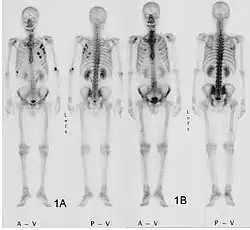

- Vues de fractures pathologiques

Fracture pathologique de l'humérus sur une métastase de carcinome du rein

Fracture pathologique du bras gauche sur une métastase osseuse de cancer du sein

Scintigraphie corps entier avec 99mTc-HDP de la patiente avec une fracture du bras due à une métastase du cancer du sein

La scintigraphie osseuse est actuellement encore le meilleur moyen de diagnostic des métastases osseuses. Ce procédé est relativement sophistiqué, coûteux et soumis à quelques limites diagnostiques[90]. Contrairement à la radio, on peut avec la scintigraphie représenter assez simplement l'ensemble des attaques du squelette[87]. Une scintigraphie osseuse est normalement bien plus sensible pour la détection des métastases osseuses qu'une radio. La sensibilité de la scintigraphie osseuse est assez élevée, avec 95 %. En moyenne, avec cette méthode, les métastases osseuses sont détectées six mois avant leur mise en évidence sur la radio[113]. Par contre la spécificité est substantiellement plus faible[114], car presque toutes les modifications tumorales ou inflammatoires du squelette conduisent à un enrichissement en radiotraceurs dans le voisinage. Le remodelage plus élevé et les processus de réparation dans la bordure des métastases osseuses ostéolytiques conduisent à une accumulation plus élevée du radiotraceur, visible comme un « point chaud » sur l'image de scintigraphie[115]. Un phénomène observable de rebond (flare up) peut être dû à l’augmentation de l’activité ostéoblastique au niveau des zones d’ostéolyse tumorale clinique, dont la colonisation métastatique a été éradiquée par le traitement ; il ne doit pas être confondu avec une progression métastatique, au risque de modifier le traitement de façon intempestive[116]. Dans les métastases osseuses de cancer du poumon ou du sein, la néoformation réactive d'os peut dans de rares cas être absente[117]. Sur la scintigraphie, ceci apparaît alors comme un « point froid », un domaine avec une absorption réduite du radiotraceur[118].

La scintigraphie osseuse est avant tout utilisée pour le contrôle de la thérapie, que ce soit une chimiothérapie, une radiothérapie externe ou métabolique, pour la détermination des stades, notamment pour les cancers avec tumeur primitive inconnue, et pour le suivi après cancer[87].